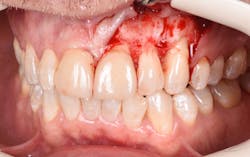

Figure 9: Initial presentation prior to crown lengthening

Figure 10: Immediate post-op hard- and soft-tissue crown lengthening with laser